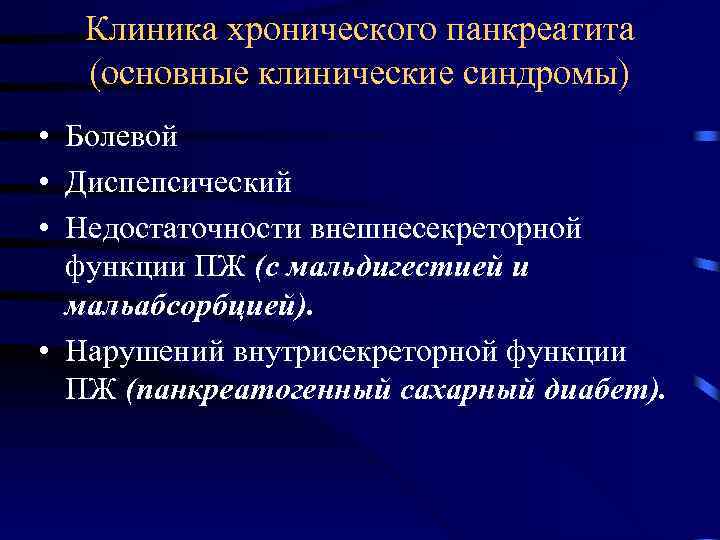

Клиника хронического панкреатита (основные клинические синдромы) • Болевой • Диспепсический • Недостаточности внешнесекреторной функции ПЖ (с мальдигестией и мальабсорбцией). • Нарушений внутрисекреторной функции ПЖ (панкреатогенный сахарный диабет).